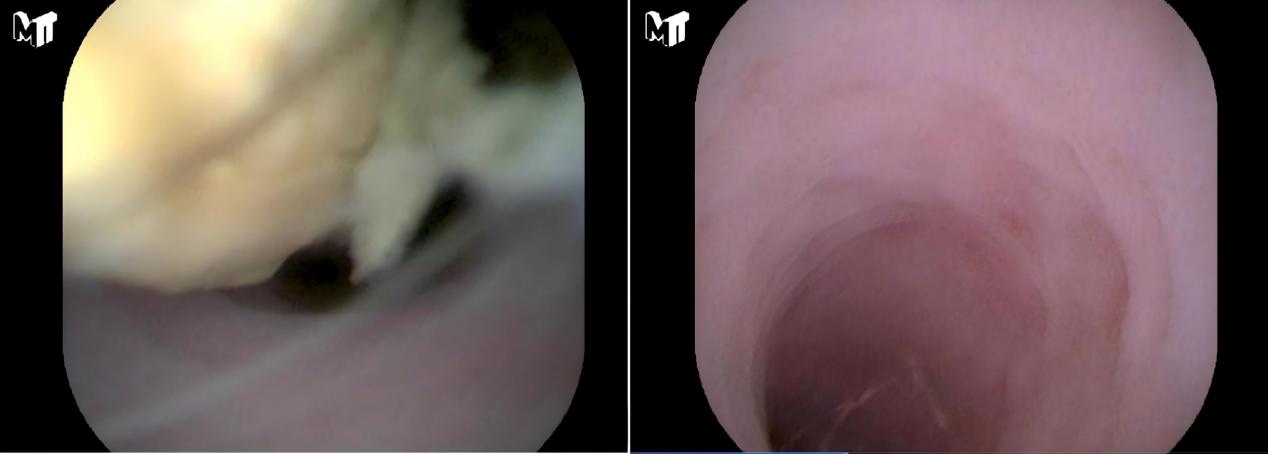

在2025年的时光卷轴上,南华大学附属南华医院以“新”为墨,以“高”为笔,绘就了一幅波澜壮阔的发展图景。当毫米级探针在腹腔深处完成精准“雕刻”,当600克的生命在掌心间重获蓬勃心跳,当国家级医疗智慧跨越山河扎根湘南,这家医院用一次次突破、一场场攻坚、一份份担当,诠释了新时代公立医院高质量发展的深刻内涵。在这里,战略的高度决定着视野的广度,积淀的厚度支撑着攀登的力度,执行的精度则转化为生命的温度。在这幅以仁心仁术为底色的壮阔画卷上,每一笔勾勒、每一处晕染,都深深镌刻着“人民至上、生命至上”的永恒初心与滚烫本色。△南华医院全景图党建铸魂,擘画发展“高度”医院发展的高度,首先体现在把准方向的政治站位与服务“国之大者”的战略视野。南华医院始终将坚持和加强党的全面领导作为医院发展的“根”与“魂”,让鲜艳的党旗在每一个临床科室、每一个服务窗口高高飘扬。这一年,党建成果硕果累累。医院荣膺“全国文明单位”“全国卫生健康系统先进集体”“南华大学先进基层党组织”等重量级荣誉,党建根基持续夯实。这一年,品牌活动浸润人心。从东洲岛畔惠及3000余人次的“中医健康夜市”,到覆盖珠晖区、衡南县17家医疗机构的“党建红·健康绿”七一巡回医疗;从“一支部一品牌”的生动实践,到党支部深度参与科室重大决策的制度落地,党建活力如春雨润物。全年发布新闻4000余条,在《光明日报》、央视新闻、《健康报》等媒体频频发声,2次亮相湖南卫视《新闻大求真》,品牌影响力与美誉度持续攀升。这一年,队伍锻造坚实有力。医院不仅选派骨干援疆、助力乡村振兴,还多次组织中层干部专题培训,锻造忠诚干净担当的管理中坚。建立院领导与党外人士常态化联络机制,汇聚发展合力。青年团员深入基层开展义诊超百人次,充满人文关怀的“单身青年联谊交友”活动温暖人心。2024年度国家三级公立医院绩效考核满意度测评荣获满分,这“百分”口碑,绝非偶然,它是党建引领下医德医风建设日积月累的硕果,是万千患者用信任投出的最温暖、最有力的一票。△中医夜市△联影全景数字PET-CT技术攻坚,开拓生命“深度”面对疾病的未知疆域与生命的脆弱时刻,南华医院选择以技术创新为利刃,勇闯“无人区”,挑战“不可能”,在多个关键领域实现了从“跟跑”“并跑”到“领跑”的华丽转身,不断拓展着生命护佑的深度与广度。微创介入,抵达“毫米”之境。2025年5月,消化内科胡杨教授团队在腹膜后“禁区”施行超声内镜引导下细针穿刺活检术(EUS-FNB),如“刀尖之舞”取出关键组织。该技术已纳入医保,一年为62名基层患者明确诊断,平均节省14天。目前,医院正在筹建湘南EUS培训中心,将制定标准化培训体系,通过理论授课、模拟操作等教学模式,向基层医师传播规范化EUS诊疗技术,推动区域诊疗水平提升,普惠四方百姓。生命通道,重塑“安心”之线。10月,医院血液净化团队针对血管条件极差、资源几近耗竭的患者,创新性融合应用“B超实时引导”与“扣眼穿刺”技术。这项结合了实时可视化与隧道化优势的技术,为最棘手的患者带来了100%的穿刺成功率。此外,医院在静脉治疗领域也取得突破,成功开展全市首例“一针式”隧道PICC置管术。外科手术则向“无痕”精准再进阶。乳甲外科吕鹏飞主任开展“免充气经口腔镜甲状腺癌根治术”直播,吸引超3万同行观摩。心脏大血管外科张毅主任在湖南省内较早开展“充气纵隔镜联合腹腔镜食管癌根治术”,为食管癌患者提供更优选择,主动脉夹层手术量达到市内领先。精准影像,赋能诊疗“导航”。医院核医学科的“精准医疗革命”持续深化,随着“核医学诊疗工作推进示范项目”通过中期评审,PET-CT等十余项创新技术将功能与解剖影像深度融合,推动肿瘤、心脑血管疾病的诊断效能迈上新台阶,为临床决策提供了至关重要的“导航图”。极限救治托起“掌心”希望。新生儿科在2025年多次创造了生命的奇迹。11月,一面锦旗诉说着一个孕26周、出生体重仅600克的超早产儿“安安”的故事,也彰显着危重症救治实力。从出生“黄金1小时”的集束化管理,到NICU内模拟宫内的精细化环境调控与疼痛管理,团队成功助其闯过呼吸、感染、营养等重重生死关卡,历经80余天,体重增长至2040克,顺利出院。这不仅是医疗技术的胜利,更是对生命极限的深情致敬。△“全球前2%顶尖科学家”程丹(右一)指导医学生做实验聚智夯基,累积学科“厚度”致天下之治者在人才,成天下之才者在教化。医院将人才资源视为第一战略资源,将学科建设作为立院之本、强院之基,通过引育并举打造“人才雁阵”,通过顶层设计构建“学科高原”,为可持续发展注入源源不断的智力动能和体系支撑。海纳百川,打造人才集聚“强磁场”。医院柔性引进3位长江学者,实现国家级人才新突破;引入多名临床特聘专家及团队,有力支撑临床发展与学科建设。全年引育高层次人才及博士20人,其中程丹再度跻身全球前2%顶尖科学家行列,吕鹏飞获评湖南省芙蓉计划卫生健康青年人才。全院博士总数突破百人,高素质人才梯队日益雄厚。攀峰筑原,构建层次分明“学科群”。2025年,医院以战略眼光优化学科布局,推动学科体系实现能级跃升。神经内科成功入选湖南省医学学科建设项目C类学科;全年获批15个省级临床重点专科及建设项目。至此,一个定位清晰、层次分明、优势互补的“金字塔”型学科体系巍然成形:塔尖是4个国家临床重点专科建设(含培育)项目,代表着医院的顶尖实力与攻关方向;塔身是1个省医学学科建设项目、15个省级临床重点专科(含建设项目),构成了医院高质量发展的中坚力量;塔基是10个院级重点专科,作为后备军蓄势待发。从“省级重点”到“国家级重点”的质变,标志着医院学科“高峰”耸立、“高原”坚实的格局已然形成。名家入驻,擘画专科发展“新蓝图”。2025年,两大国家级顶尖团队的加盟,为医院专科发展按下了“加速键”。中山大学肿瘤防治中心长江学者特聘教授唐玲珑团队多位湖南籍专家定期回乡开展义诊与临床指导工作,让广大群众在家门口就能享受到高水平、高质量的医疗服务。北京大学第一医院杨旭教授其团队入驻后,将重点帮助医院建设多学科眩晕诊疗中心、推行标准化前庭功能检查流程、培养专科人才,将助力建立真正的MDT模式,让湘南地区的患者不必远行,就能获得全面、精准的诊疗。这些全国知名的医疗团队和专家的加入,为医院专科发展注入了全新的活力,也为未来的学科发展和人才培养奠定了坚实的基础。这些“国家队”的深度融入,不仅带来了前沿技术,更引入了先进的诊疗理念与管理模式,为医院相关学科的跨越式发展装上了强大的“外脑”引擎。 研教协同,淬炼创新“精度”问渠那得清如许?为有源头活水来。科研与教学,是医院永葆活力、引领未来的源头活水。2025年,医院在这片沃土上深耕不辍,实现了从量的积累到质的飞跃,以科研的“精度”驱动临床诊疗走向更深层次的精准。科研立项,实现从“高原”到“高峰”的跨越。医院在科研项目申报与立项上取得突破性进展。全年获批国家自然科学基金项目5项、湖南省自然科学基金项目52项,立项数量与质量均创历史新高,并实现了重点项目的新突破。此外,还成功立项科技部国家重点研发计划子课题,呈现出项目类型多元化、覆盖领域广的良好态势。全年承接药物临床试验(GCP)项目67项,为临床转化研究提供了重要平台。前沿探索,闪耀智慧之光。基础研究与临床应用的桥梁日益畅通,10月,临床研究所、生物分子影像研究室程丹研究员团队在肿瘤诊疗领域取得重大突破,在国际权威期刊发表成果。团队在交叉学科领域同样建树斐然,成功开发新型荧光探针,首次实现了对环境污染物诱导胰岛素抵抗全过程的动态可视化监测,搭建了环境健康与代谢疾病研究的新桥梁。7月,廖勇仕教授参与的跨机构研究团队,在顶级期刊《Nature Biomedical Engineering》上发布了大规模泛癌血浆蛋白质组图谱。该研究系统分析了数千例癌症血浆样本,深度揭示了癌症的分子特征,并在此基础上开发出高精度诊断模型,为癌症的早期筛查与诊断开辟了一条全新路径。育才树人,桃李芬芳。教育教学工作是医院可持续发展的根基。2025年,医院研究生教育质量稳步提升,其中多人获评国家奖学金及省、校级优秀毕业生、干部等荣誉。在湖南省首届住院医师规范化培训临床技能竞赛中,医院代表队荣获团体“三等奖”及个人一、二等奖,展现了扎实的临床教学功底。隶属医院的核工业卫生学校,在技能竞技场上同样捷报频传:在2025年世界职业院校技能大赛总决赛中斩获金奖1项、银奖1项;在“楚怡杯”湖南省职业院校技能竞赛中获得一等奖3项、二等奖2项;更有一个创新创业项目成功晋级黄炎培创新创业大赛国赛。这一系列成绩,是医院“医、教、研、产”四位一体协同发展模式结出的丰硕果实。△联网自助系统服务赋能,传递惠民“速度”作为区域医疗中心的“排头兵”,南华医院始终将公益性写在旗帜上,将改善患者体验落在细微处。通过智慧化建设提“速”,通过资源共享扩“面”,通过公益行动传“温”,让医疗技术的发展高度,切实转化为人民群众可感可及的健康福祉与民生温度。智慧医疗,让“信息跑”替代“患者跑”。医院上线医保刷脸支付、床旁结算系统,患者等候时间缩短10%以上。104项检验结果实现区域互认,让数据多跑路,患者少奔波。智慧化建设,正从流程优化入手,于细微之处体现着以人为本的服务理念。资源下沉,将“国家队”水平送到“家门口”。医院主动将优质医疗资源向基层延伸,构建多层次医疗保障网络。牵头组建“珠晖区城市医疗集团”,积极探索“一体化管理、同质化服务”的区域医疗协作新模式。与省内多家县级人民医院深化医联体合作,全年新签订14家工伤医疗服务协议,扩大服务覆盖。这种下沉不仅是技术输出,更是危急时刻的“生死驰援”:通过远程会诊平台,指导基层医院成功实施高难度手术抢救危重孕产妇;派出多学科博士专家团队星夜赶赴县级医院,现场主导抢救80岁动脉瘤破裂危重患者,将不可能变为可能。△健康科普△基层义诊公益担当,在更广阔天地书写仁心。医院的担当,不止于院墙之内。从举办全国性“蛇伤中毒规范化诊疗培训班”,提升基层医务人员对危急重症的救治能力;到组织医护团队深入社区、企业、学校,开展上百场形式活泼的健康科普讲座与义诊;再到一批又一批医疗专家胸怀大爱,奔赴援疆、援非医疗一线,将先进的医疗技术和深厚的南华情谊播撒在祖国边疆和非洲大陆。医院的辐射力、影响力,正随着医者仁心的足迹,不断向更远、更需要的地方延伸。回望2025,南华医院的每一步攀登,都在诠释对“高度”“深度”“厚度”“精度”“速度”五个维度的深刻理解与实践。从党建铸魂的政治高度,到技术攻坚的生命深度;从人才学科体系的积淀厚度,到科研教学的创新精度;再到惠民服务的传递速度,共同构成了医院高质量发展的立体坐标与完整拼图。展望前路,风正潮涌,自当扬帆破浪;任重道远,更需策马扬鞭。站在新的历史起点,南华大学附属南华医院将继续秉持这份初心与担当,在深化党建引领、强化人才战略、攀登学科高峰、优化运营管理、提升服务品质的征程上,奋楫笃行,臻于至善。医院必将以更加昂扬的姿态、更加坚实的步履,绘制出更高质量、更富内涵、更有温度的发展新蓝图,为守护湘南地区及更广泛区域人民的生命健康,为全面推进“健康中国”建设的宏伟事业,贡献更加璀璨、更加磅礴的“南华力量”与“南华智慧”!